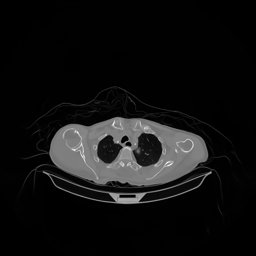

The results for simulated noisy data are shown in Fig. 2. The first and third rows display two representative slices from the test set, and the second and fourth rows present the corresponding error maps. The traditional WCE method suppresses cupping artifacts and recovers some missing anatomical structures but still shows noticeable deviations from the ground truth. Predictions from the four diffusion-based models demonstrate a markedly improved ability to restore anatomical structures. Among them, cDDPM fails to fully reconstruct the patient bed and retains residual noise in its outputs. This noise is attributable to an incomplete reverse denoising process rather than residual Poisson noise, as evidenced in our noise-free experiments (Fig. 5 in the Appendix). PatchDiffusion, diffusionGAN, and I2SB achieve similar visual quality, with I2SB producing the cleanest and most consistent reconstructions.

The experimental results on clinical head data are shown in Fig. 4. The reference images were reconstructed using the fast iterative shrinkage-thresholding algorithm (FISTA) with total variation regularization from non-truncated projection data. In the WCE reconstructions (Fig. 4(b)), severe truncation prevents accurate recovery of anatomical structures outside the FOV. Despite being trained solely on simulated data with a domain gap, all deep learning models can restore a substantial portion of the missing anatomy. Among them, the diffusion-based methods recover soft-tissue boundaries more faithfully than the conventional deep learning approach FBPConvNet, highlighting their stronger image generation capability. However, cDDPM reconstructions exhibit more noticeable noise than those from other methods, consistent with the simulated data results. The patchDiffusion model introduces artifacts within the FOV, likely due to its patch-wise processing strategy. While I2SB shares the same limitations as other diffusion models in perfectly restoring soft-tissue detail, it produces fewer residual noise patterns and fewer artifacts within the FOV boundaries. Overall, Fig. 4 demonstrates the strong efficacy of I2SB in reconstructing real CBCT data.